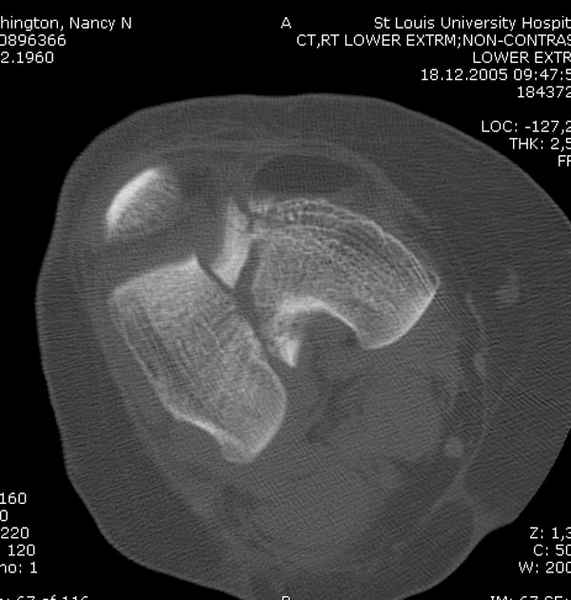

При наличии различных имплантов, любые варианты: слева (полу) открытым - мининвазивным, а справа закрытым интрамедуллярным методом, его считаем более чем приемлемым для фиксации данных переломов.

Проксимальная и дистальная блокировка, независимо от техники введения штифта, ретроградно или антеградно, гарантирует сращение сегментарных переломов бедра без укорочения. Штифты диаметром 12 мм с блокировкой сверху и вниз двумя шурупами выдерживают вес 75 кг больного, что позволяет раннюю профилактику контрактур.

Погоня за "красивой рентгенограммой" не всегда оправдана для фиксации кости, где имеется массивное мягкотканое покрытие. Если так уж хочется исправить положение кости, то при наличии ЭОП, большие костные фрагменты могут быть развернуты или приближены к основному фрагменту методом применения Joystick.

Главное в лечении сегментарных переломов - необходима осторожность при рассверливании канала, продвижение гибкого сверло через сегмент проводят без сверления, толканием, а то были случаи, когда весь сегмент крутился вместе со сверлом.

Из-за вариабельности установки дистальных шурупов и возможности перкутанного введения проксимально предпочитаем DePuy Polyax, хотя на сегодняшнем маркете множеств вариантов фиксации дистального бедра перкутанном методом.